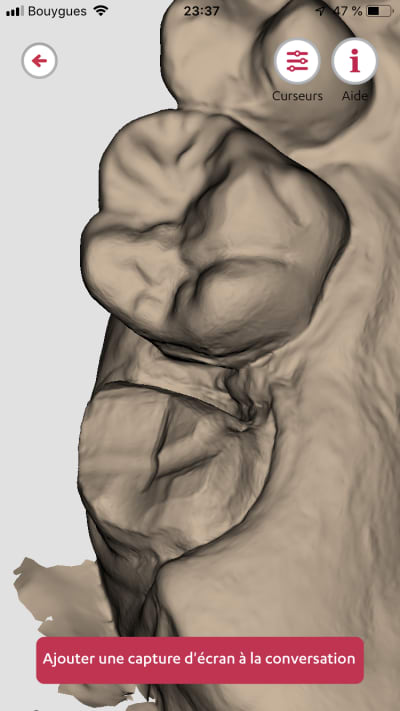

Exemple de ce sue sort une trios 2 de 2013..

Un exemple de scan avec matching emp pour richmond tenon anatomique sous stellite.

> Pas mal pour une vielle dame ! ?

> Les zones proximales entre 6 et 7 ..

Trios 2 couleur de 2013...